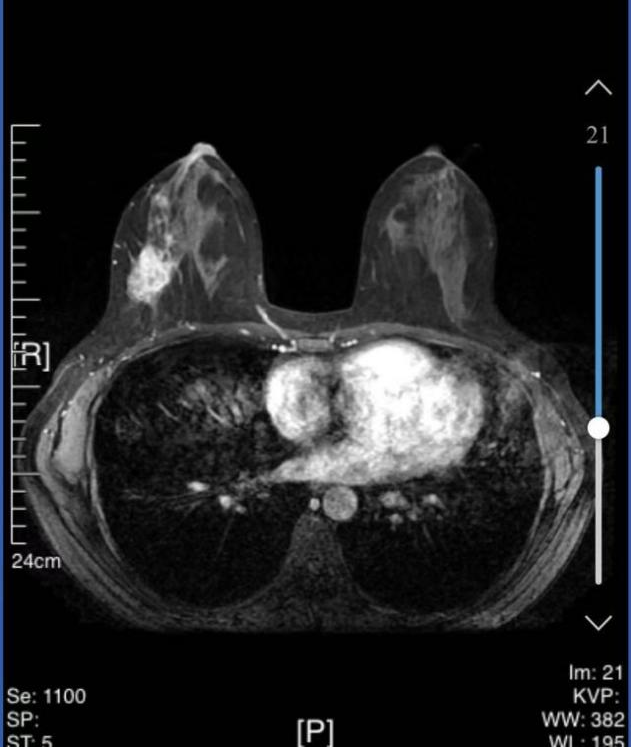

• 乳腺核磁共振(MRI):

1、右乳外侧象限见T2WI稍高信号肿物,大小约31mm*25mm*33mm,形态不规则,边缘分叶;内部强不均匀,TIC曲线初始呈快速强化,延迟期呈平台型;DWI呈高信号,ADC值为0.000811mm2/s。右腋窝见肿大淋巴结。

MRI提示:右乳外侧象限肿块及多处非肿块样强化,BI-RADS 5类;右腋窝淋巴结肿大。

图3 乳腺MRI结果(2024-03-04)